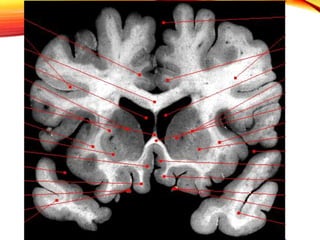

COMISURAS INTERHEMISFERICAS

• Hemisferios están unidos entre si por estructuras (Comisuras

interhemisfericas)

CUERPO CALLOSO

• impar de sustancia blanca de considerable espesor en la

profundidad de la fisura longitudinal cerebral. Se

extiende de un hemisferio al otro y se prolonga en el

centro semioval (sustancia blanca) de cada hemisferio.

CONSTITUCIÓN

ANATÓMICA

• Tractos anteriores se condensan en la rodilla y forman el

fórceps mayor

• Tractos medios constituyen el tapetum que forma la pared

lateral del atrio, el hasta temporal y elasta occipital del

ventrículo lateral

• Tractos posteriores. Provienen de la parte posterior de la

corteza occipital. Se agrupan en la parte posterior y forman

el fórceps mayor.